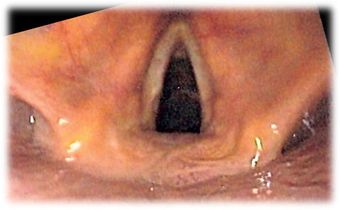

صورة Endoscopic للحنجرة | |

Endoscopic image of larynx seen at the time of intubation of the esophagus during gastroscopy.